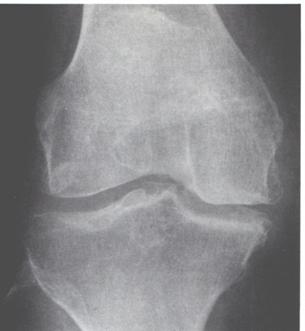

DIAGNOSI

|

In fase precoce è affidata alla RMN, mentre la radiologia tradizionale mostra le fasi più avanzate del processo. |